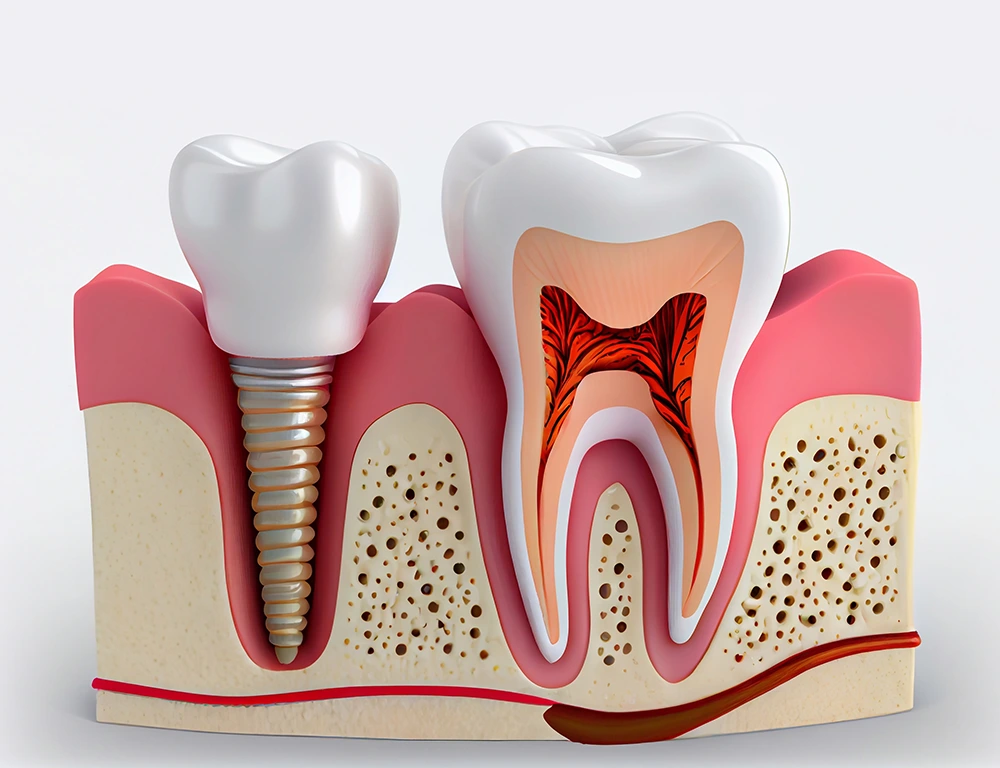

Implantodontia

O que é implante dentário?

Consiste em reconstruir um ou mais dente(s) perdido(s) através da implantação cirúgica de "pinos" no osso da maxila ou mandíbula. Esses "pinos" são os implantes de titânio. Os implantes dentários atuam como as raízes dos dentes perdidos. Um material biocompatível (não sofre rejeição) com nosso organismo. Posteriormente sobre os implantes dentários é instalada uma peça protética.